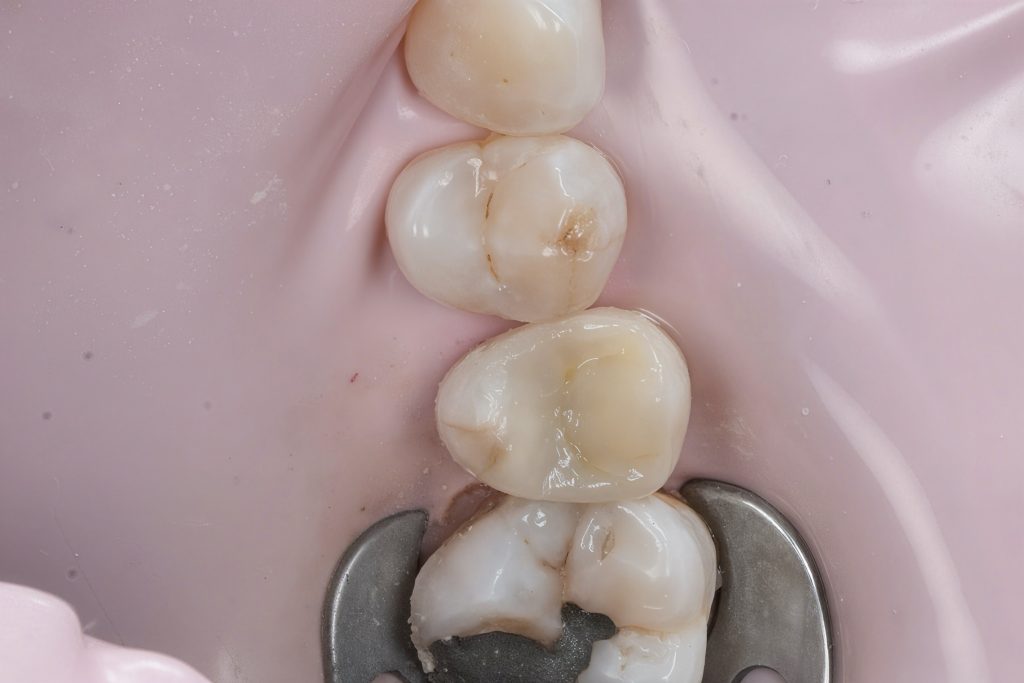

Defective composite and caries were removed in a controlled manner preserving sound enamel walls. Teflon floss ties and wooden wedges used for separation and gingival retraction (Fig 3–6).

3. Matrix System Placement

Sectional matrix system used to recreate anatomical proximal walls. Ring stabilization applied to ensure tight contact and optimal emergence profile (Fig 7–8).

- Initial caries exposure and removal

- Proximal clearance and wedge placement

- Matrix placement and isolation refinement

- Sectional ring application